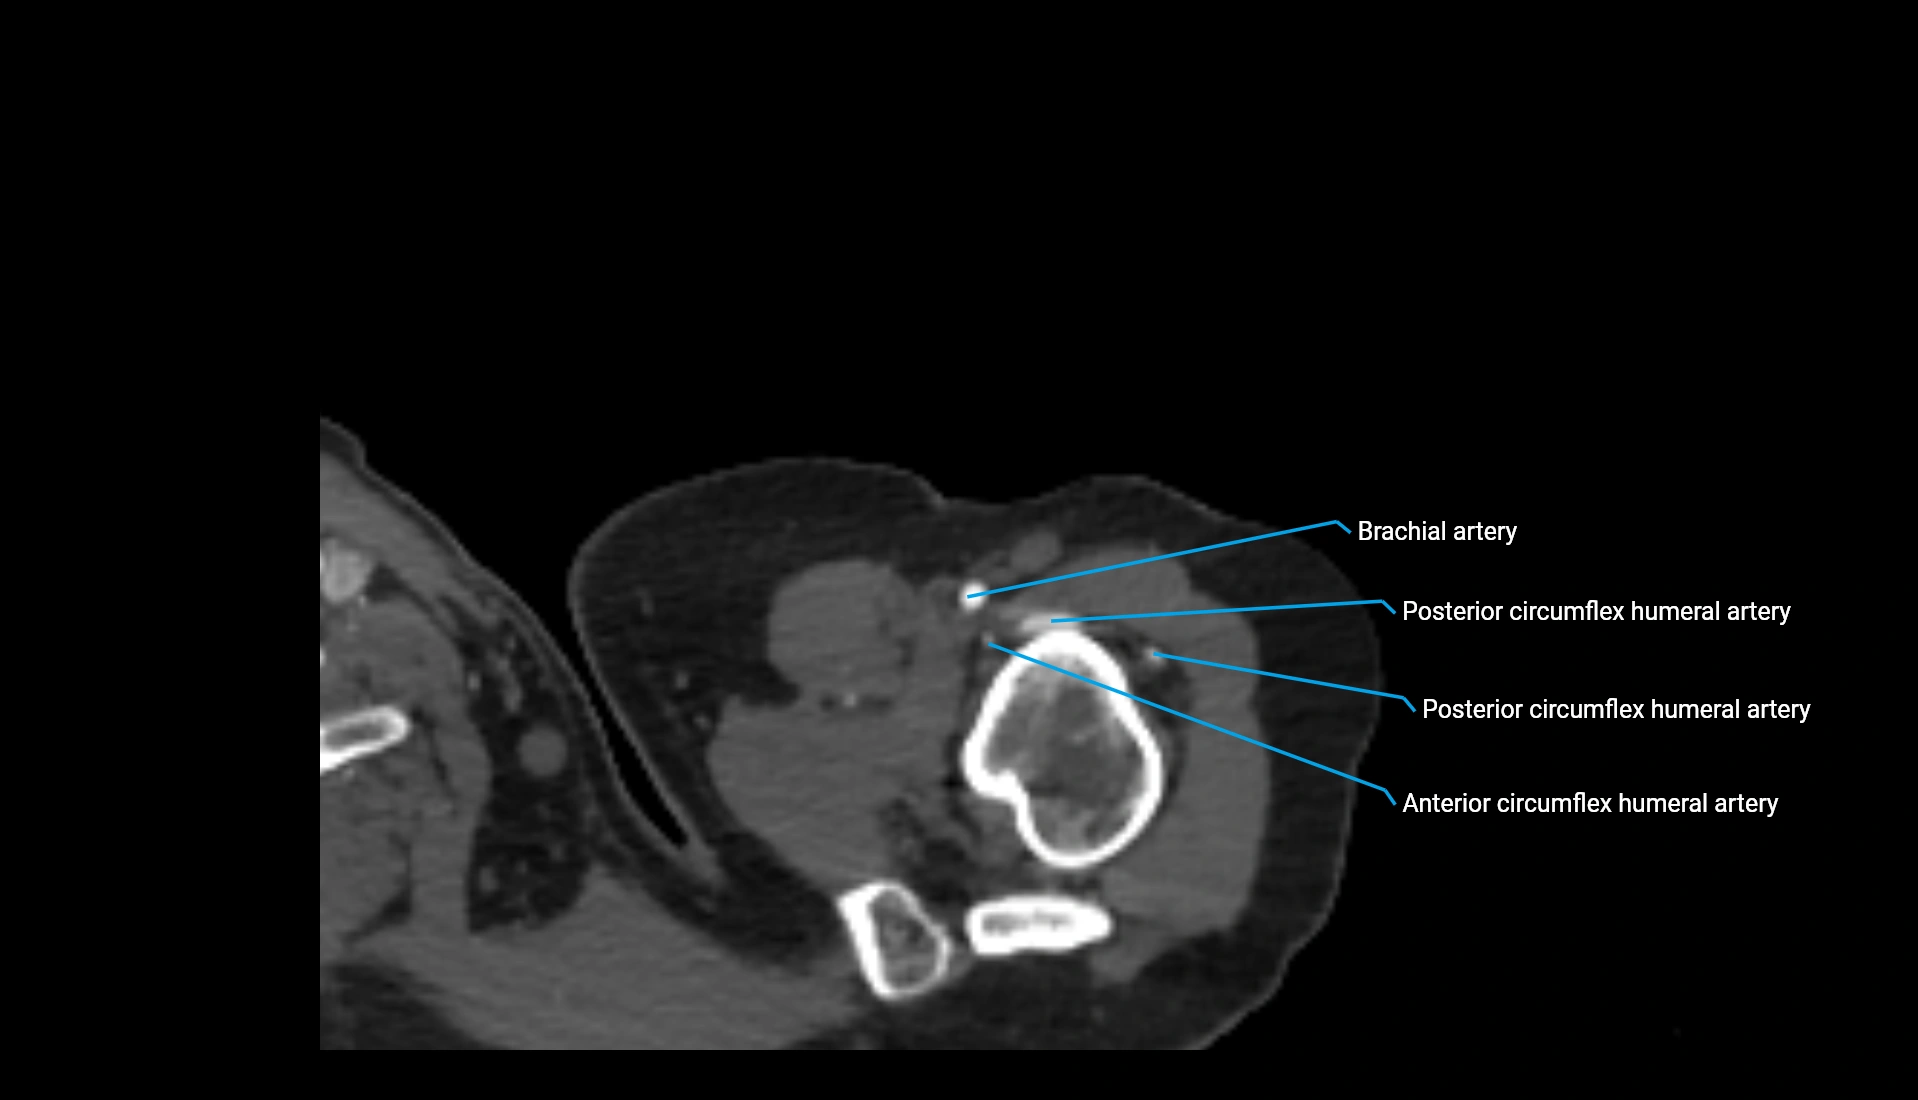

CT Appearance

Non-Contrast CT:

• Cortex: High-density, sharply defined

• Subchondral bone: Dense cancellous matrix

• Articular surface: Smooth concave contour articulating with the capitellum

• Excellent for evaluating bone integrity, alignment, and subtle fractures

Post-Contrast CT:

• Bone: No enhancement

• Joint capsule and synovium: Mild enhancement outlining the joint

• Improves contrast between soft tissues and bony margins

• Useful in detecting subtle joint abnormalities or postoperative changes